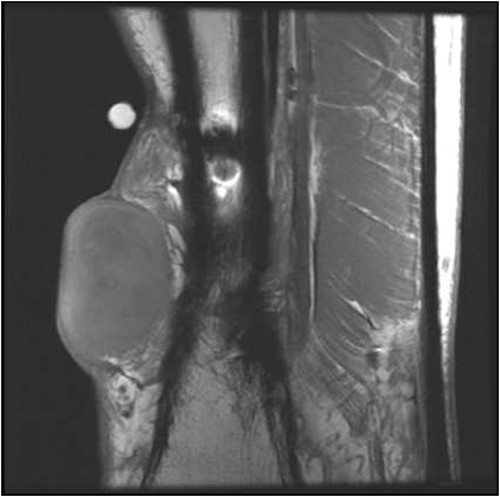

He presented upon noticing a lump overlying the rectus flap. On exam, the left lower extremity had multiple incisions with well-healed scars and a protruding lesion at the distal aspect of his previous incision, which was non-tender to palpation (Fig. 1). MRI of the lower extremity revealed a soft tissue mass in the anterior compartment of the left lower extremity (Figs 2 and 3). Biopsy of the lesion demonstrated RMS and molecular diagnostics revealed missense mutations in MYOD1 (p.L122R) and DOT1L (p.G1441R). Tumor cells were microsatellite stable. The copy number profile is suggestive of broad copy number gain of chromosome 5p. The patient was discussed at the local tumor board and was treated with D9803 chemo protocol (vincristine-based), receiving 4 cycles before proceeding to operative management.